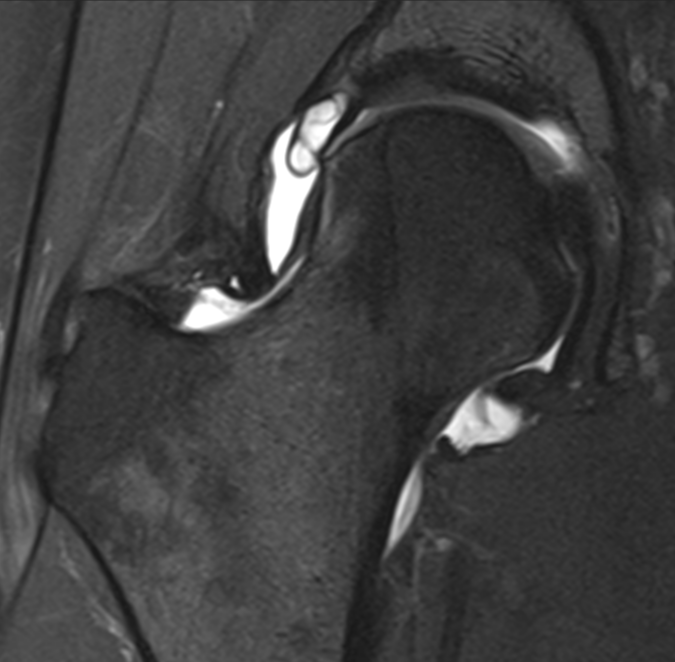

3. Torn acetabular labrum with intralabral cyst